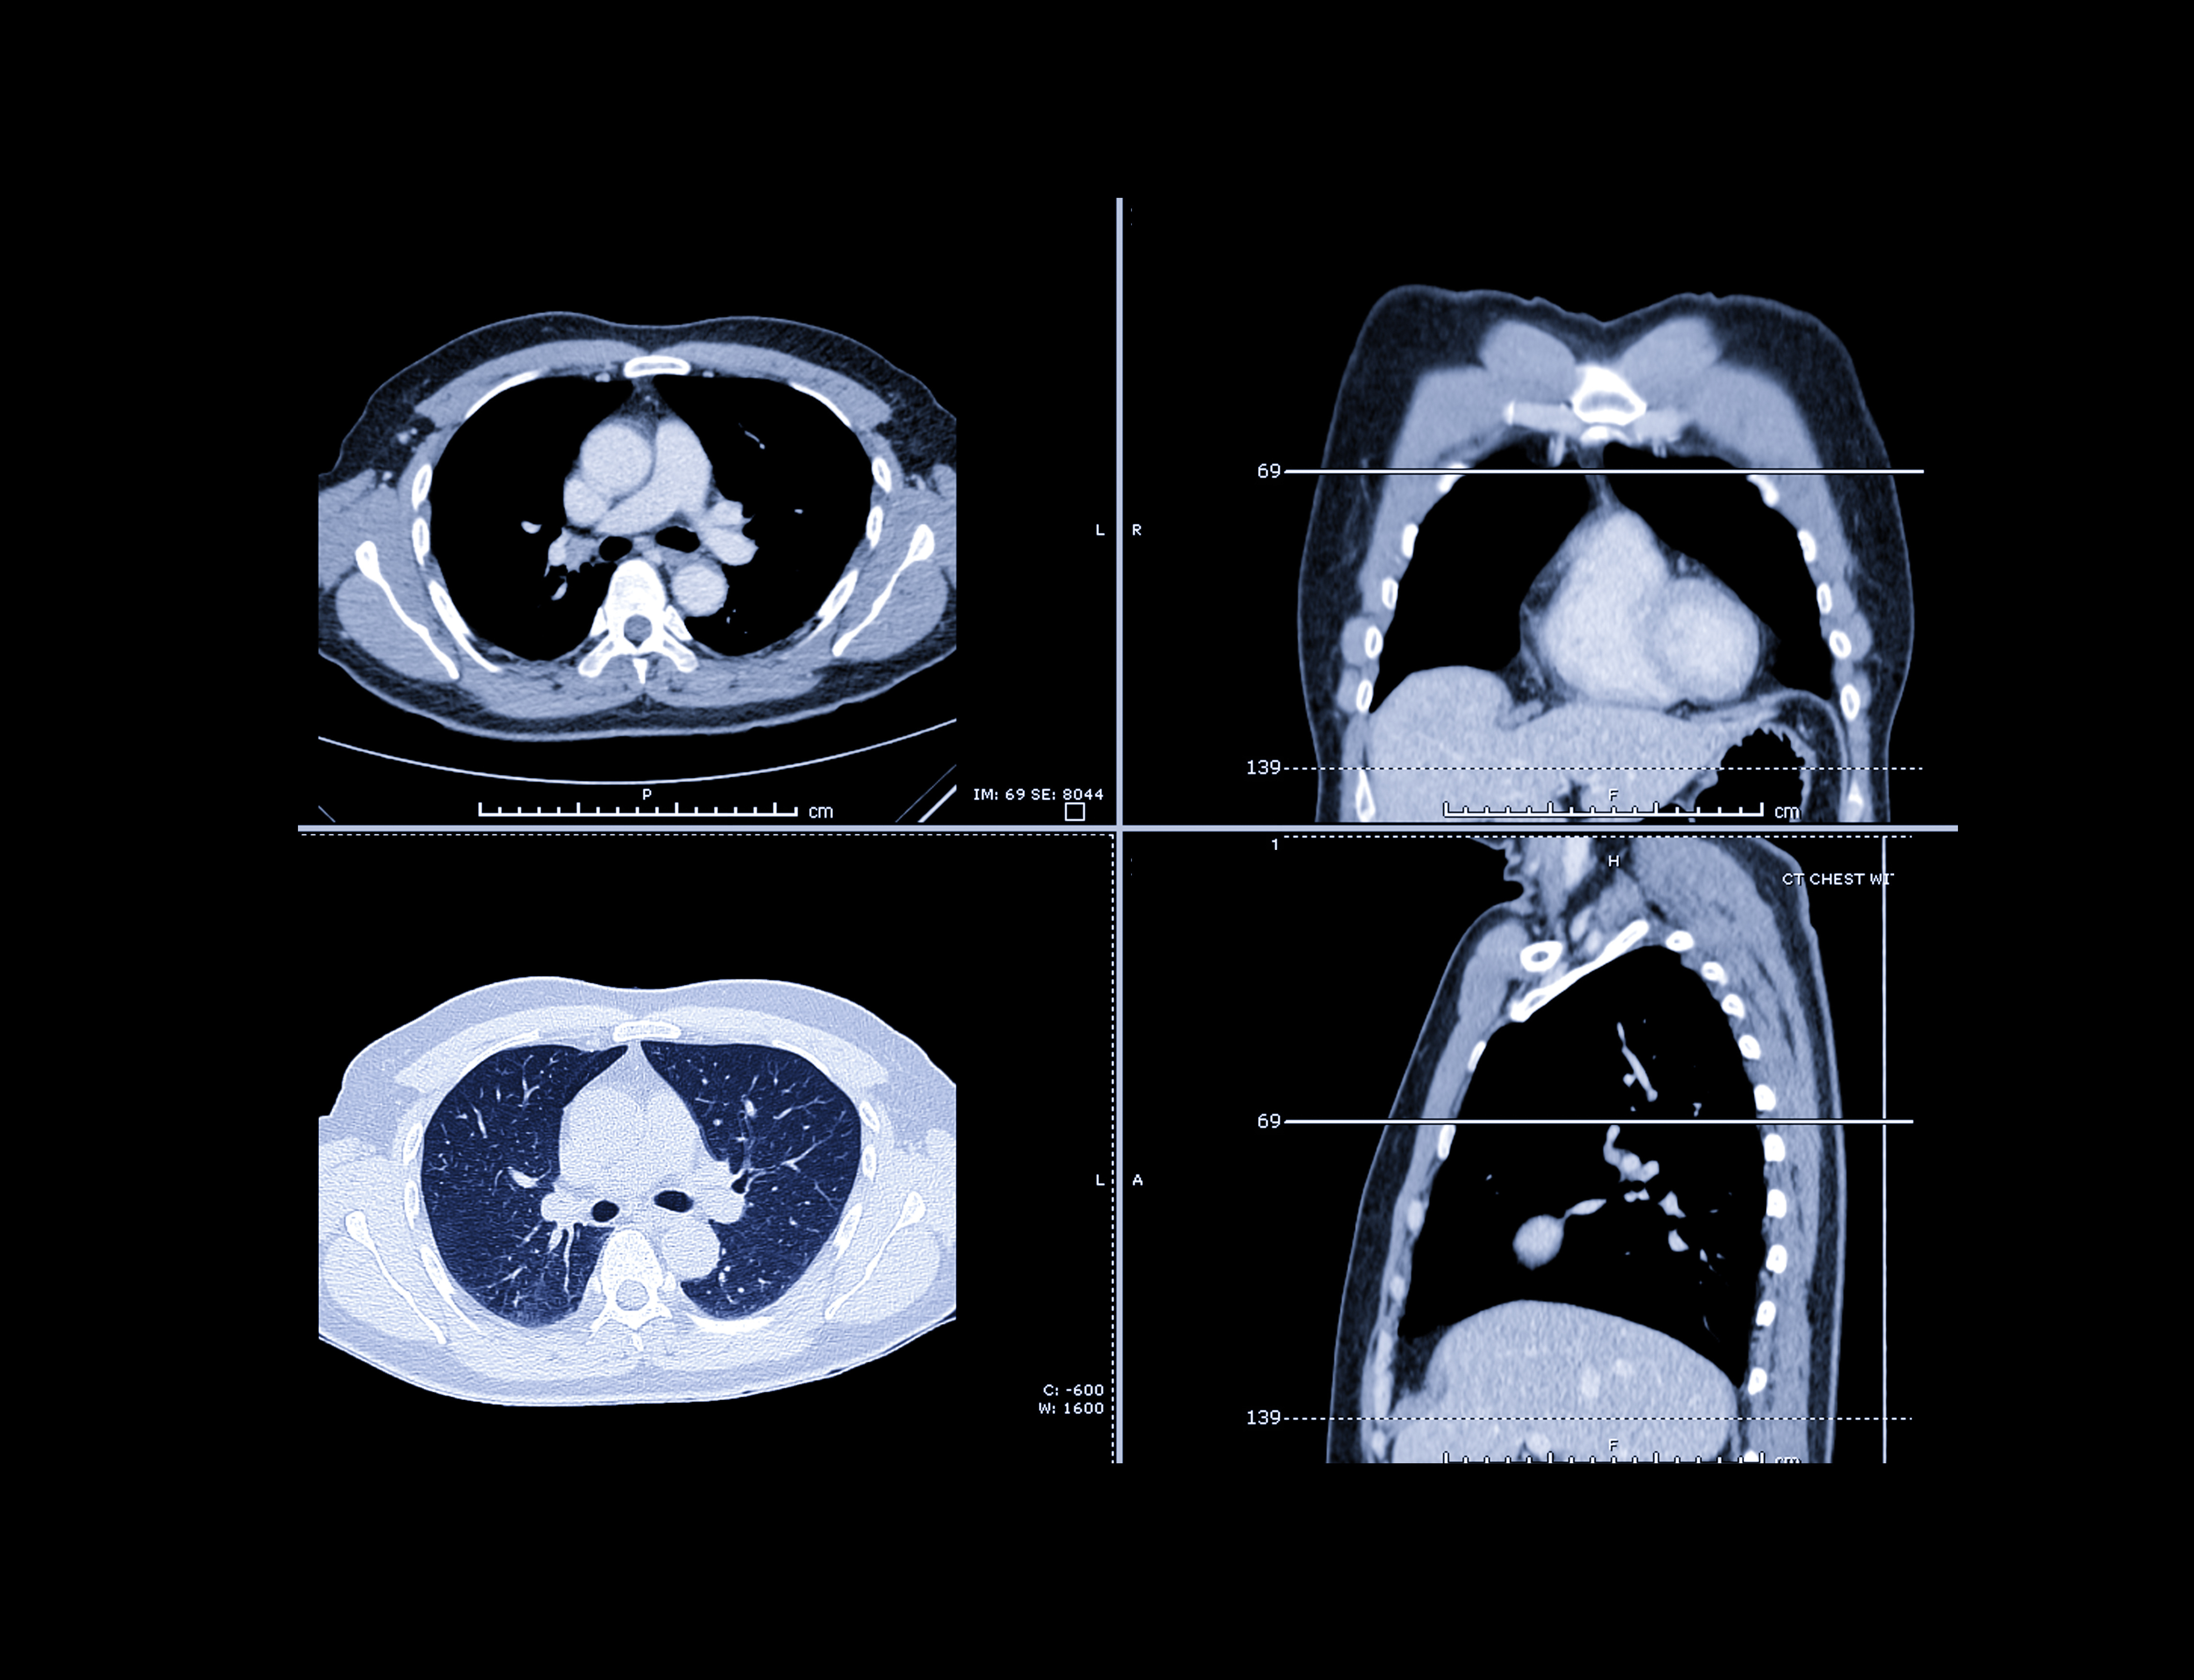

Cancer risk assessment and treatment management software developer CancerIQ plans to partner with Azra AI to support lung cancer screening by blending risk-based patient identification with AI-powered low-dose CT (LDCT) follow-up.

CancerIQ helps radiology departments and cancer centers identify patients who may benefit from lung cancer screening, assess individualized risk, educate patients, and guide appropriate LDCT scheduling. Azra AI's enterprise platform uses AI to help radiology teams to track actionable findings, prioritize follow-up, and manage patients, according to the two firms.